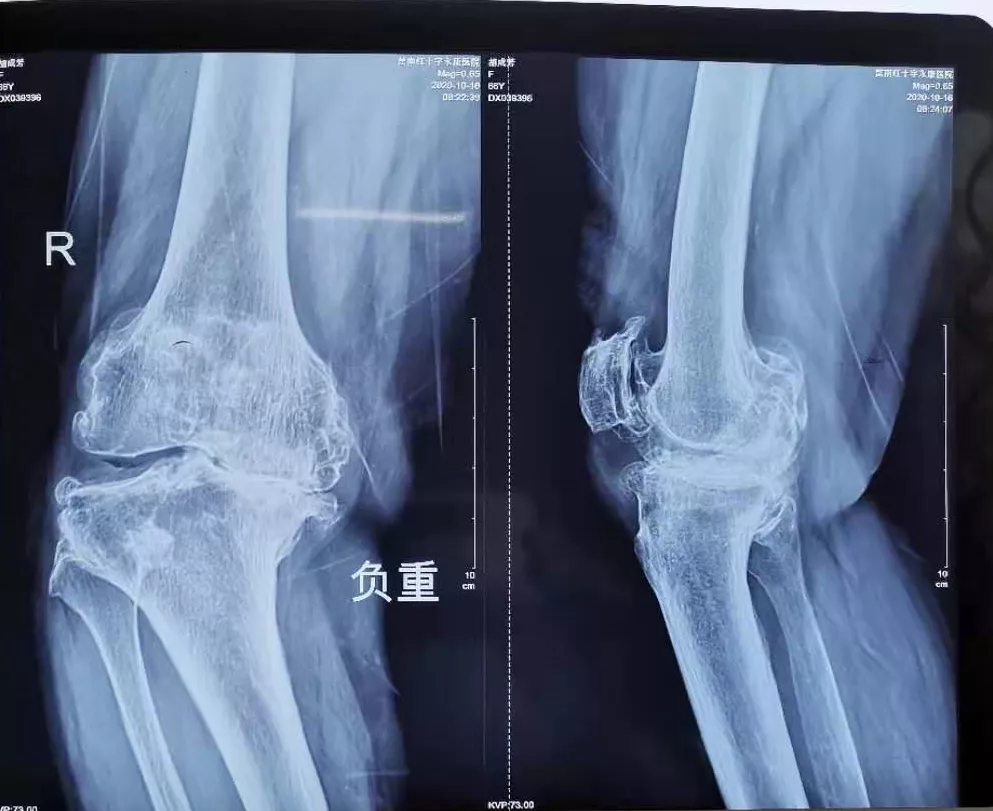

病例一:

患 者:女,76岁。

主 诉:双侧膝关节疼痛10余年,伴渐进性加重的畸形和活动受限。曾长期行不规范的保守治疗。

查 体:左膝活动范围20°~40°,HSS评分35分;右膝活动范围25°~40°,HSS评分30分。

检 查:术前负重位X-ray显示双膝重度骨性关节炎合并屈曲内翻畸形。

术前影像:

术前正位

术前侧位